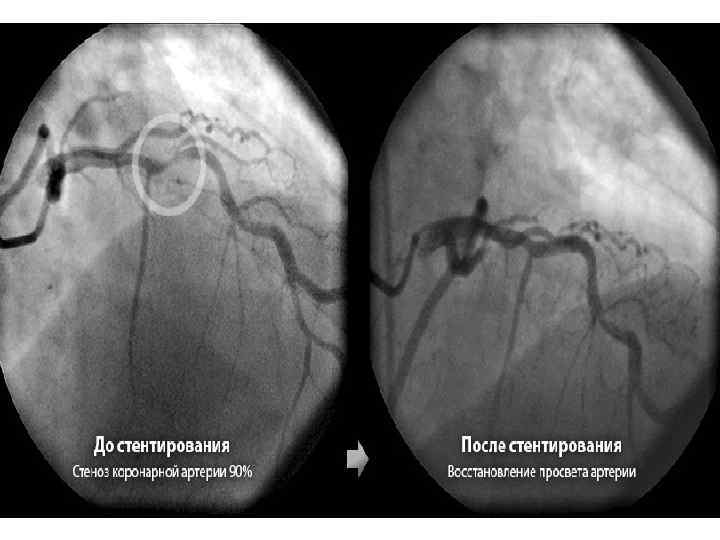

ХИРУРГИЧЕСКИЕ МЕТОДЫ ЛЕЧЕНИЯ. • Хирургическая реваскуляризация миокарда (ЧТКА, АКШ) улучшает выживаемость б-х ИБС с тяжелым течением иили прогнозом заболевания. Различают клинические и ангиографические показания их применения. Клинические показания – отсутствие эффективности медикаментозной терапии стенокардии, сохранение симптомов ИБС, резко ограничивающих физическую активность пациентов. Ангиографические показания: 1. Трехсосудистое поражение КА; 2. 2 -3 -сосудистое поражение КА в сочетании с дисфункцией ЛЖ; 3. Поражение ствола ЛКА; 4. ФВ<30% независимо от количества пораженных КА. Показания к применению ХМЛ у пациентов пожилого и старческого возраста следует определять тщательнее, чем у лиц среднего возраста из-за большего риска осложнений.